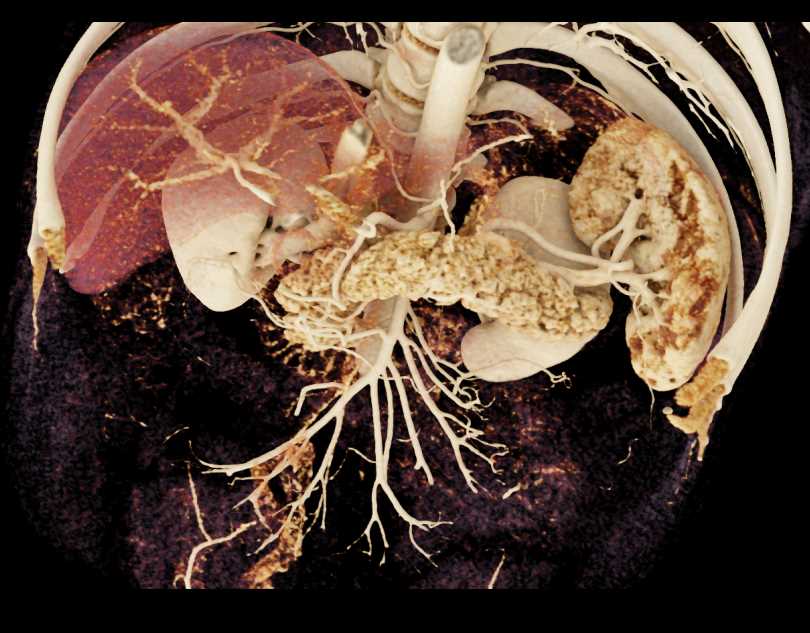

Subtle Neuroendocrine Tumor Body of Pancreas